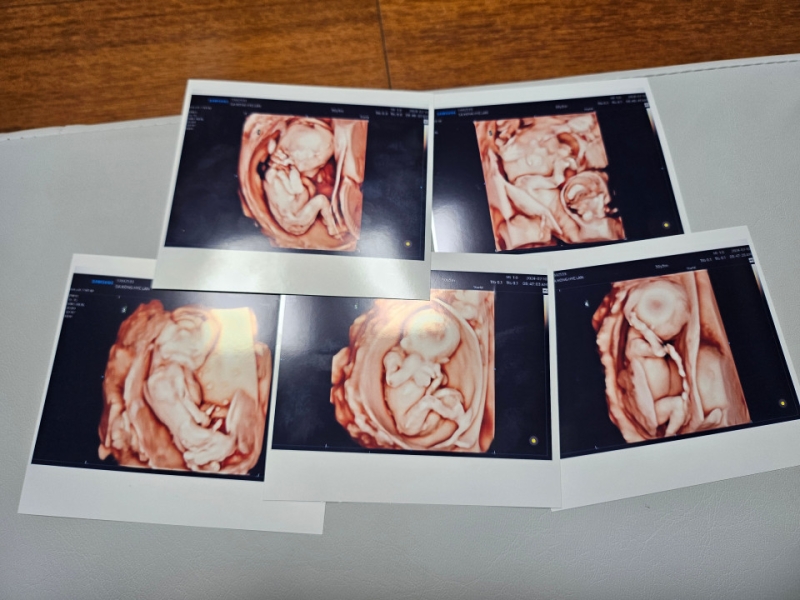

저출산 문제가 심각한 상황에서 자연임신으로 생긴 다섯쌍둥이가 건강하게 출산하는 경사가 생겼습니다.

20일 서울성모병원에 따르면 이 병원에서는 이날 낮 남자아이 3명과 여자아이 2명의 '오둥이'가 건강하게 태어났습니다.

더구나 이날 태어난 다섯 명의 아기들은 자연임신으로 생겼습니다.

국내에서 다섯쌍둥이가 자연임신으로 생겨 건강하게 태어난 것은 이번이 처음입니다.

아기들의 모친은 결혼 후 임신을 준비하기 위해 찾은 산부인과에서 다낭성 난소 증후군을 진단받고 치료를 시작했는데, 정확한 배란을 유도하는 첫 치료 후 바로 자연임신이 됐습니다.

체구가 작은 편인 산모는 예정일인 12월이 되기 훨씬 전부터 만삭처럼 배가 불렀고, 임신과 합병된 고혈압성 전자간증 진단이 나오자 더는 출산을 미룰 수 없게 돼 27주에 제왕절개 수술로 출산했습니다.